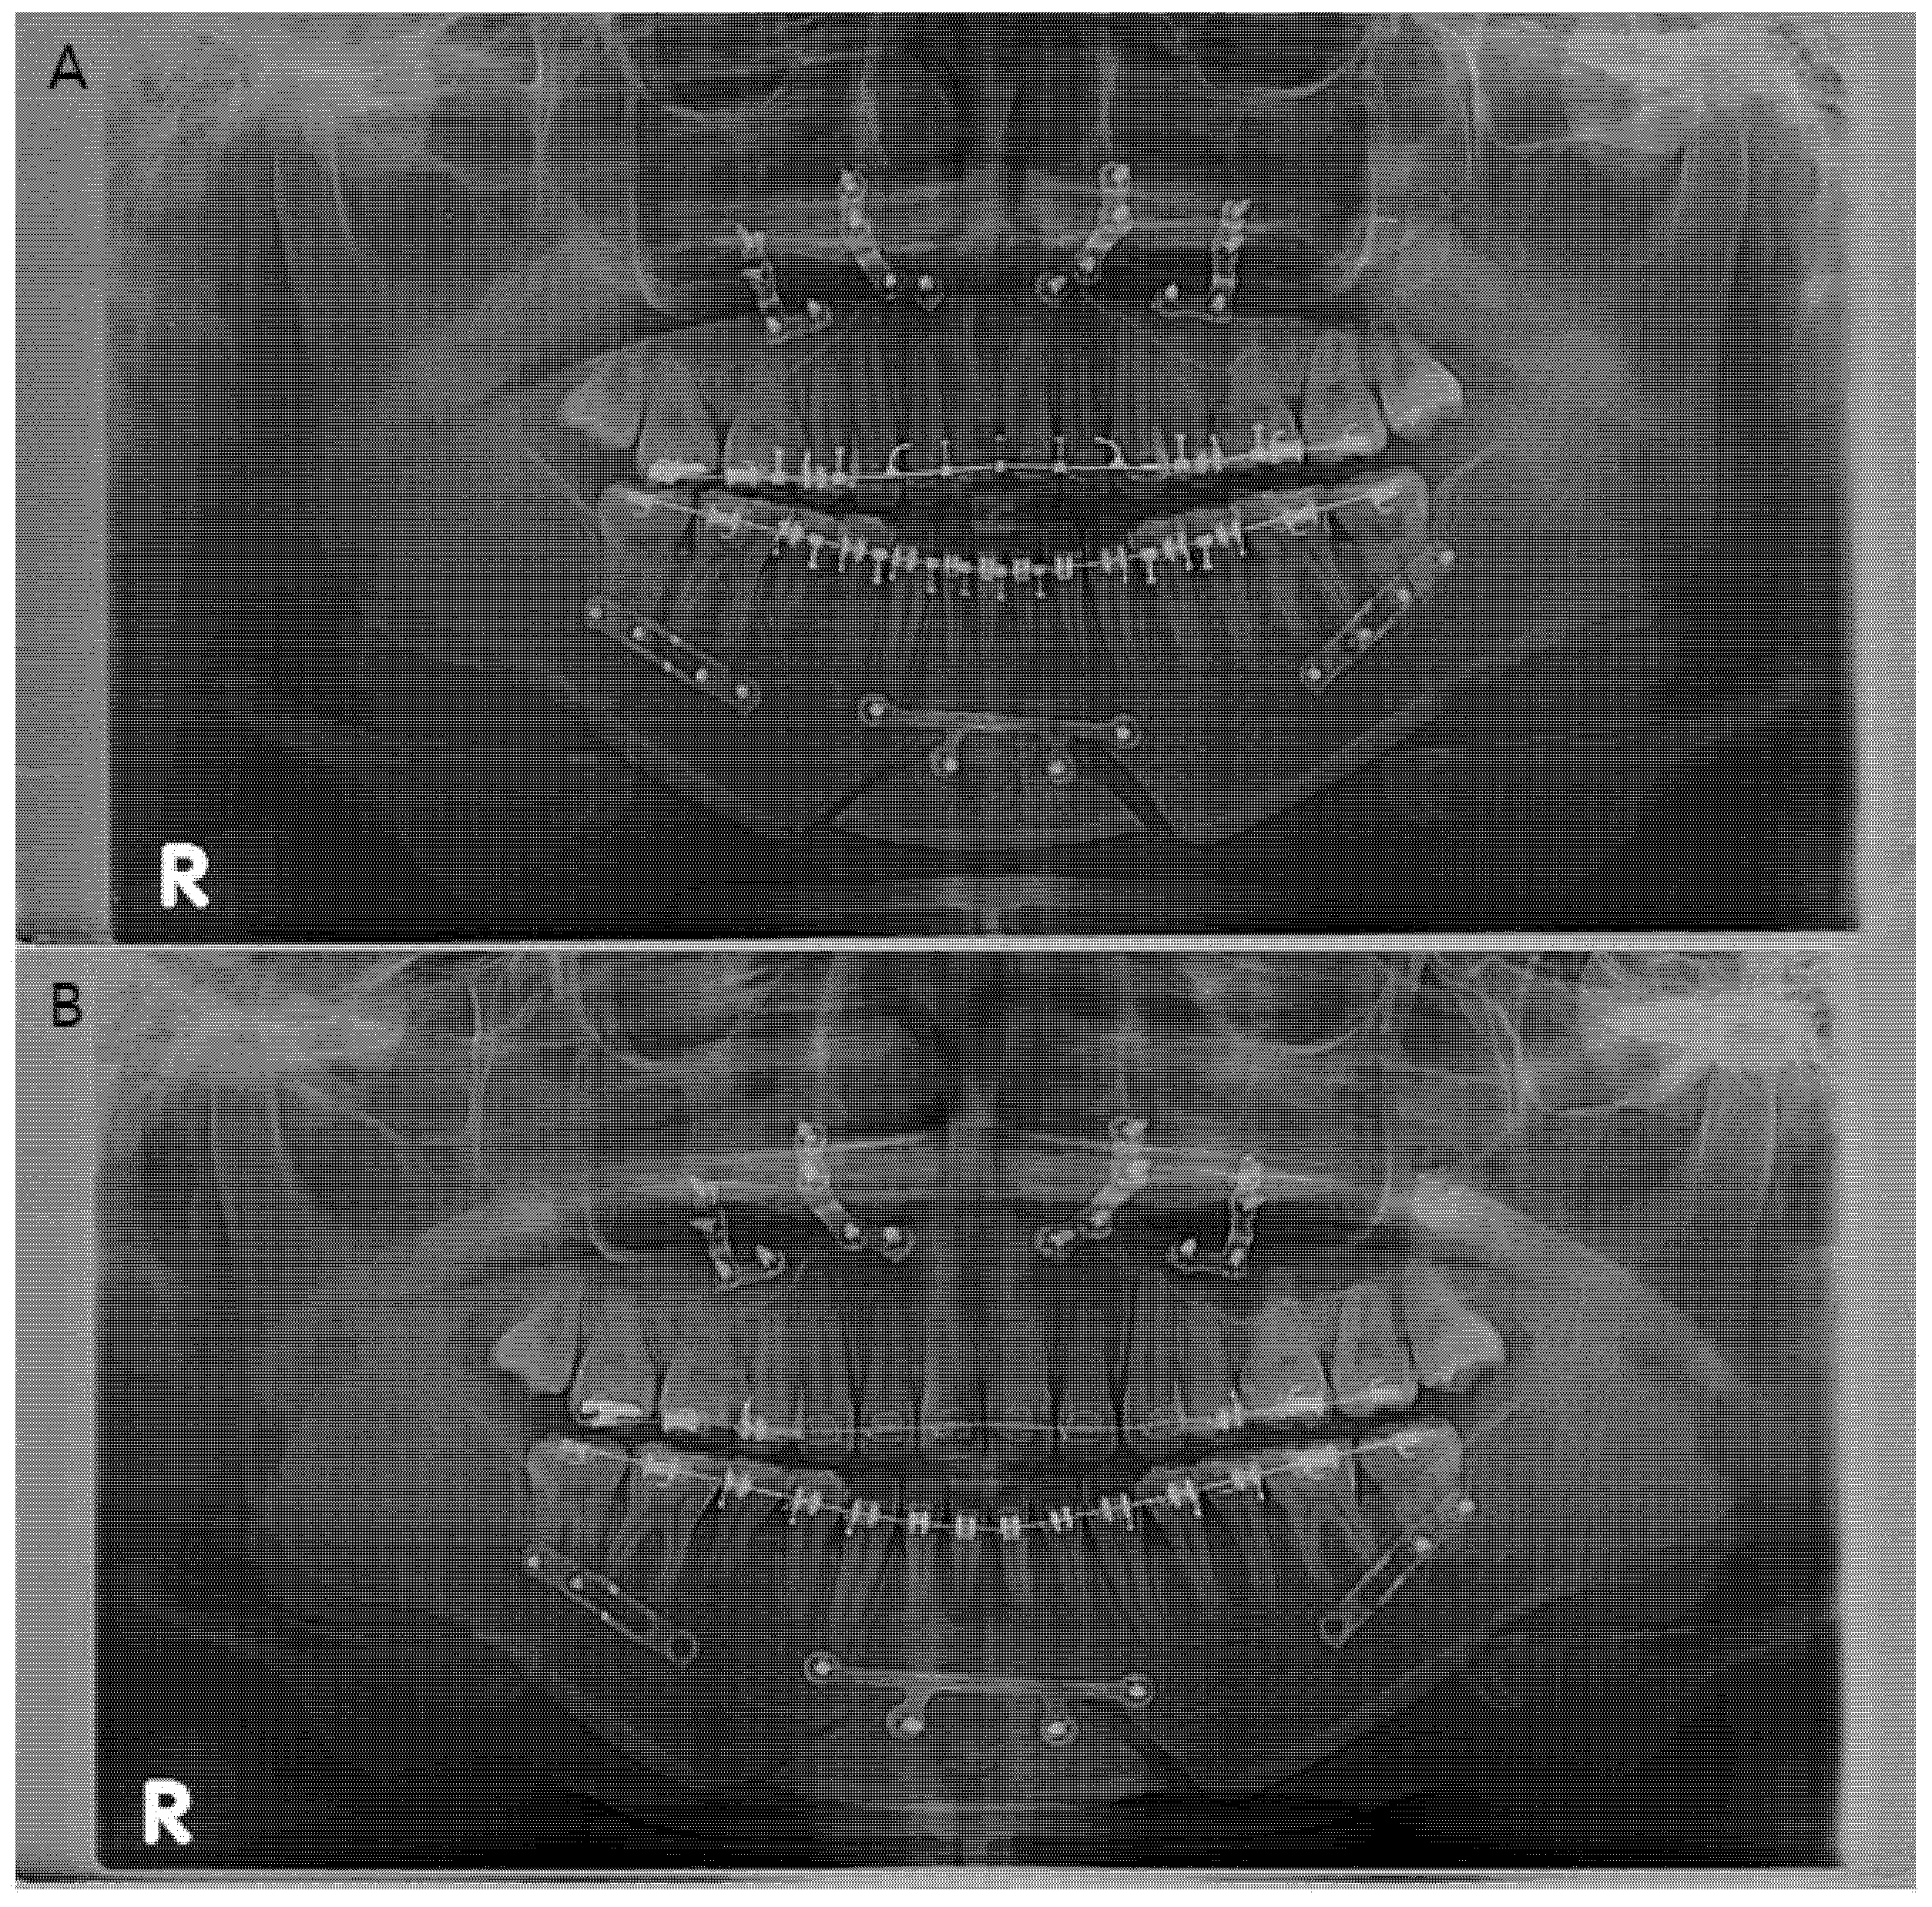

Figure 2.

(A) Panoramic radiograph of a patient (Patient no. 3) who had undergone orthognathic surgery. (B) Panoramic radiograph after early screw removal in the distal segment. “R” on the panoramic radiograph means the right side of the patient.